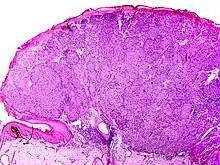

The microscopic hallmarks are:

- Dome-shaped at low power

- Epidermis thin or normal

- Dermal nodule of melanocytes with a 'pushing' growth pattern

- No "radial growth phase"